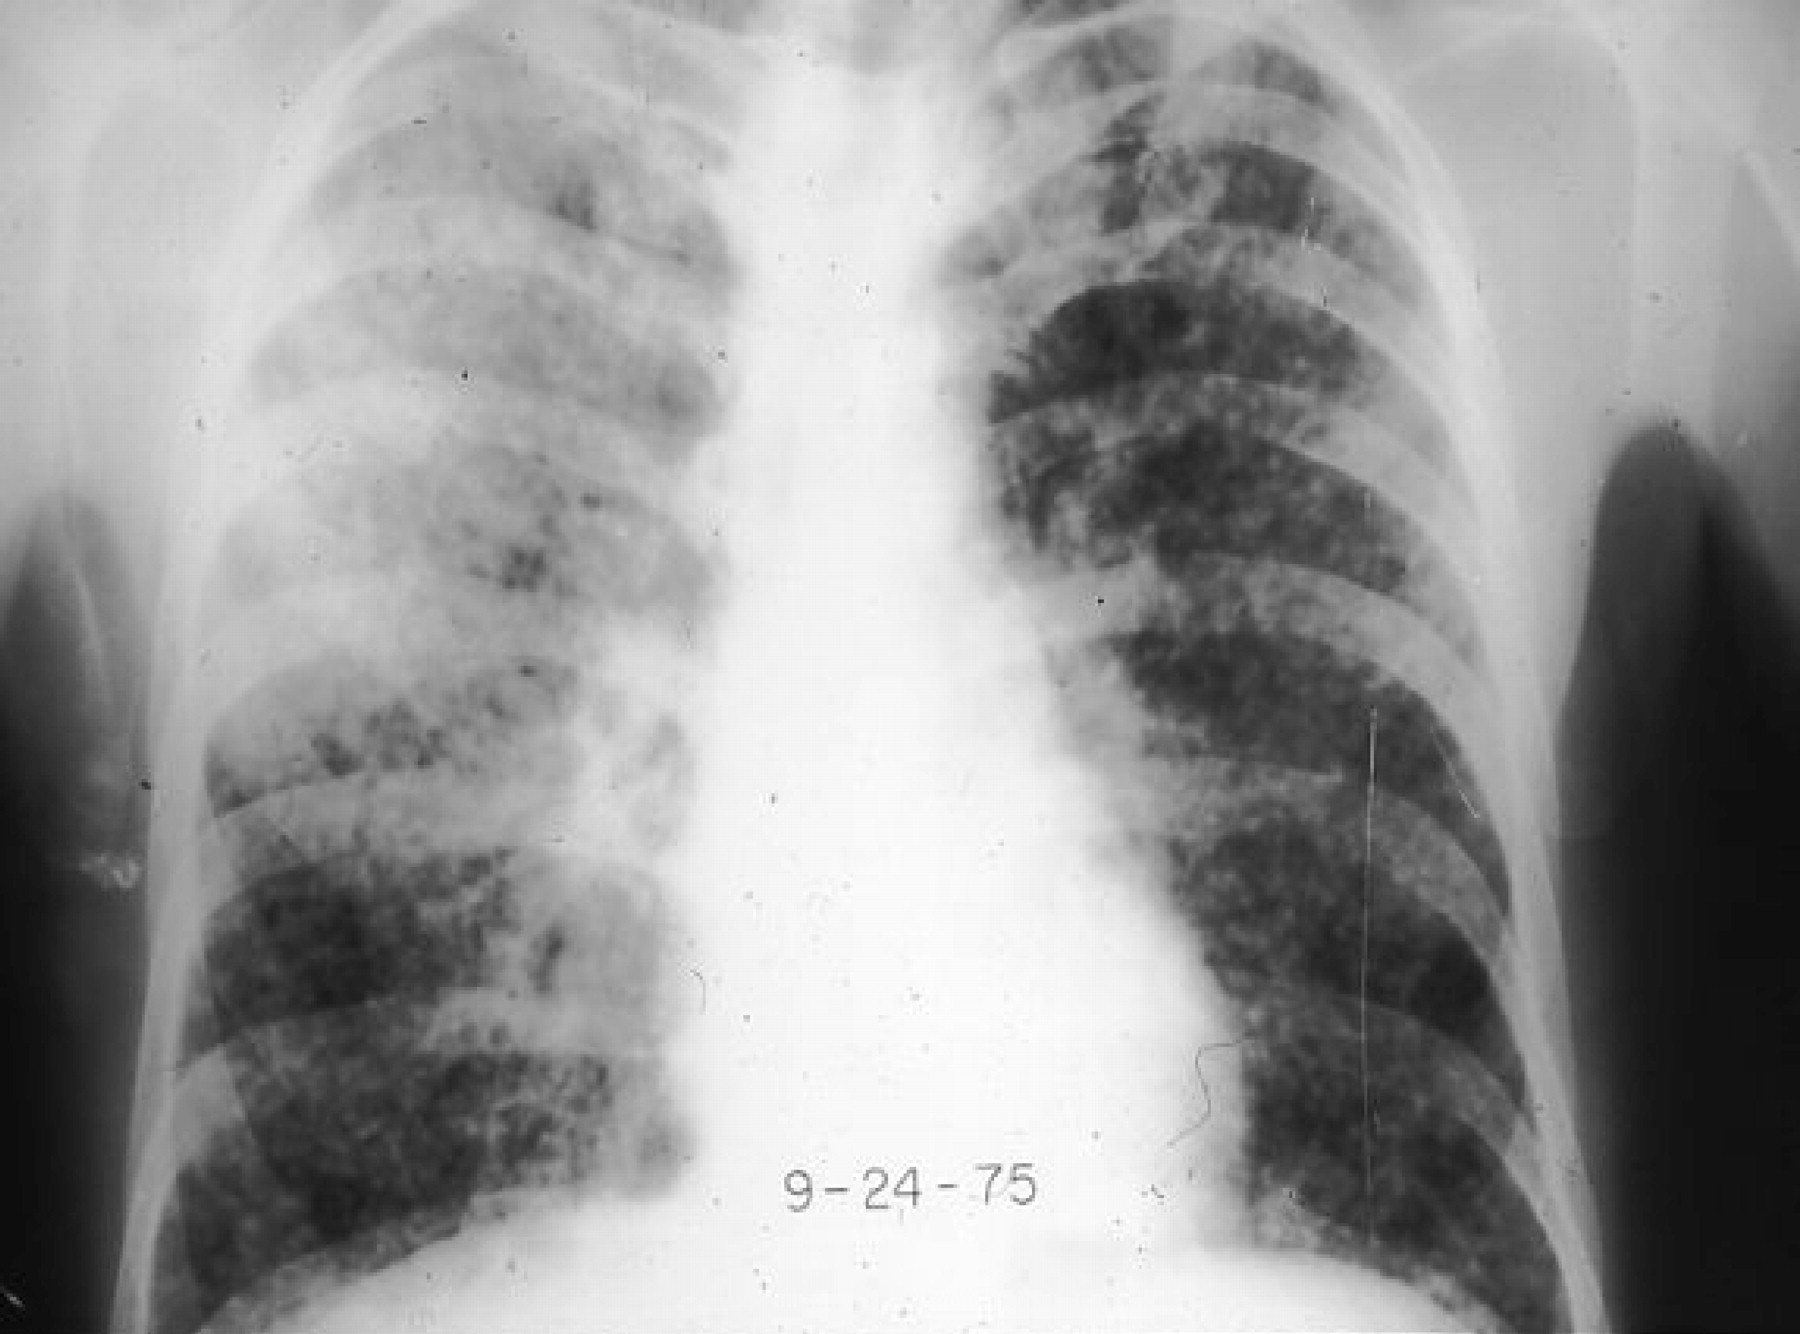

Η ακτινογραφία θώρακος δείχνει λεμφαδενοπάθεια με αποτιτανώσεις στο μεσοθωράκιο.